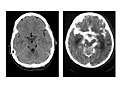

- Imaging tests. An

MRI or CT scan, which takes pictures of the inside of your

body, may show bleeding, swelling, or other changes in the brain. See a picture of a brain with encephalitis.